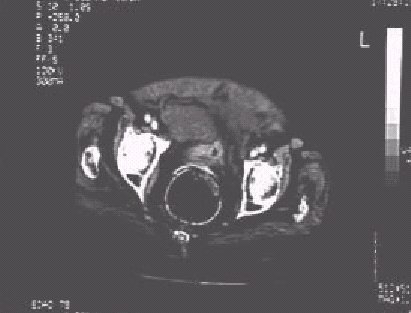

Figura 11

.—Tomografía Computerizada en una mujer politraumatizada con traumatismo pélvico. La imagen muestra un gran hematoma en región prevesical.